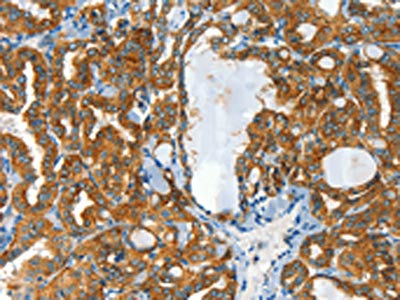

The image on the left is immunohistochemistry of paraffin-embedded Human thyroid cancer tissue using CSB-PA930031(CLPTM1L Antibody) at dilution 1/60, on the right is treated with synthetic peptide. (Original magnification: ×200)

The image on the left is immunohistochemistry of paraffin-embedded Human liver cancer tissue using CSB-PA930031(CLPTM1L Antibody) at dilution 1/60, on the right is treated with synthetic peptide. (Original magnification: ×200)